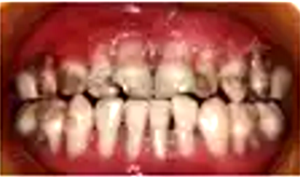

口腔專科檢查:口腔黏膜光滑,全口唇頰側(cè)牙齦重度萎縮,牙根暴露,探診易出血,牙齒表面可見齲壞及色素沉著,口腔衛(wèi)生可。遠(yuǎn)中切角缺損,Ⅱ度松動(dòng),唇側(cè)牙齦萎縮至根中1/3伴腫脹;Ⅱ度松動(dòng),唇側(cè)牙齦萎縮至根中1/3伴腫脹;冠完整,Ⅲ度松動(dòng),唇側(cè)牙齦萎縮至根尖1/3,齦乳頭及舌側(cè)牙齦萎縮程度較唇側(cè)輕(圖1)。

圖1 重型先天性中性粒細(xì)胞缺乏癥患者口內(nèi)照片